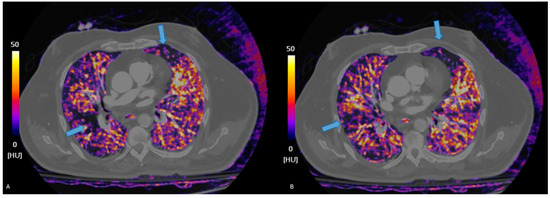

3.2. Dual Energy CT

3.2.1. Principles of DECT

3.2.2. Accuracy of DECT

- Cellina, M.; Cè, M.; Grimaldi, E.; Mastellone, G.; Fortunati, A.; Oliva, G.; Martinenghi, C.; Carrafiello, G. The role of dual-energy computed tomography (DECT) in emergency radiology: A visual guide to advanced diagnostics. Clin. Radiol. 2025, 83, 106836. [Google Scholar] [CrossRef]